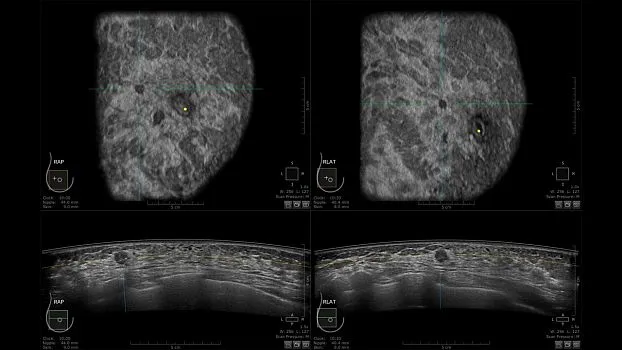

Клинические изображения

• Получение объемных 3D изображений с возможностью покадрового просмотра

• Отображение объемных 3D ультразвуковых изображений, которые состоят из традиционных поперечных и воссозданных коронарных и сагиттальных проекций

• Многооконный просмотр: 4 - 12 изображений.

• "толстый срез" в коронарной плоскости;

• поперечная;

• сагиттальная плоскость;

• радиальный и антирадиальный поворот изображения;

• просмотр только области интереса.

• Одновременный просмотр двух изображений для сопоставления в коронарной плоскости